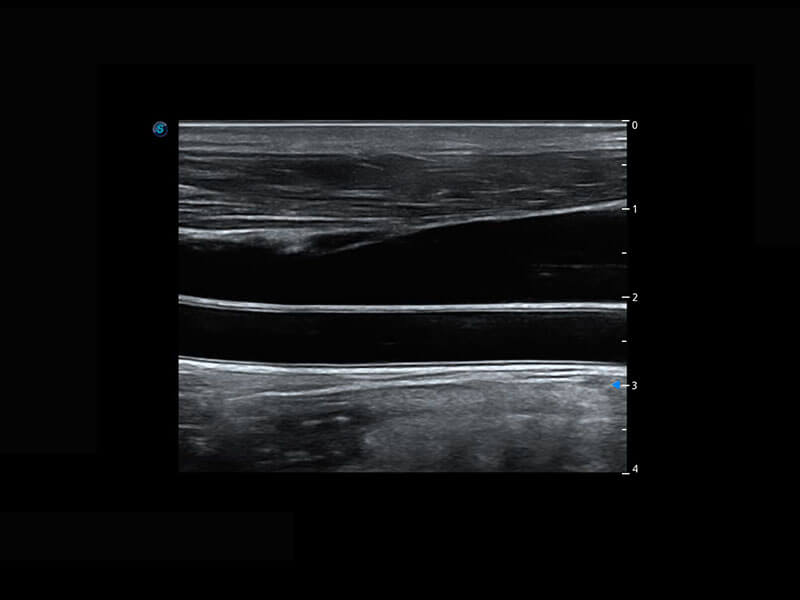

P60搭载宽频带线阵探头、宽景成像、弹性成像技术,为您提供乳腺应用方案。P60支持高频相控阵探头、线阵探头、腹部高频探头、腹部微凸探头等,丰富的探头群搭载敏感的彩色血流成像,适用于新生儿多种脏器检测要求,满足新生儿筛查需求。

乳腺导管癌

乳腺癌显微血流

新生儿肝血管癌

新生儿脊髓圆锥

新生儿心脏